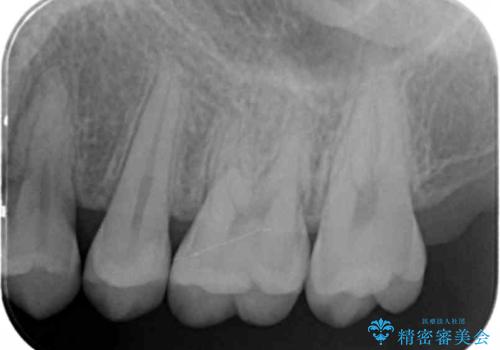

- 検査の結果虫歯が見つかった患者様です。

レントゲン画像と視診から詰め物で対応可能と判断したためインレーでの修復をしていきます。